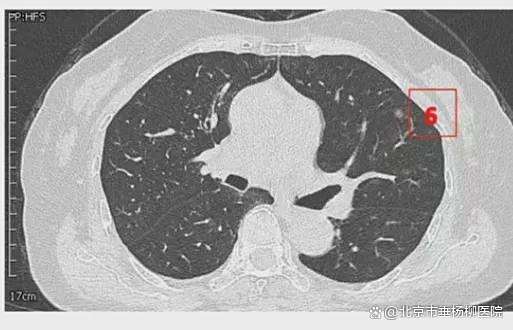

患者女性,71岁,因“发现左肺多发结节2周”入院。胸部CT提示左肺多发磨玻璃结节,较大者位于左肺上叶,呈类圆形,边界清晰,最大直径约9mm。该CT表现高度提示恶性可能。鉴于患者结节数量较多,为减少术中肺组织损伤,术前于CT引导下行经皮肺结节定位术,继而实施胸腔镜下左肺楔形切除术。术中共切除肺部结节6枚。术后病理示:左肺上叶较大结节(4号)为微浸润腺癌,其余5枚结节均为原位癌。患者术后恢复良好,于术后第1天拔除胸腔引流管,第4天顺利出院。

影像资料